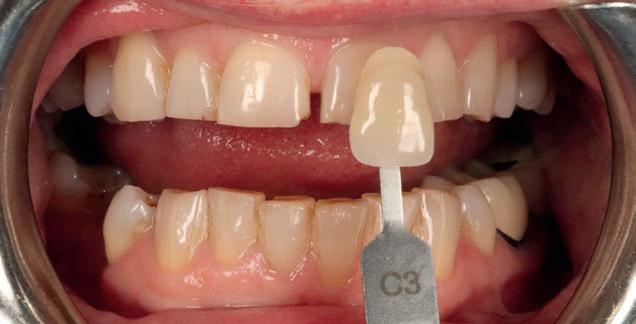

INCREASE TREATMENT ACCEPTANCE BY YOUR PATIENTS

Better understanding of the suggested treatment plan.

INCREASE TRUST AND PATIENT CONFIDENCE

Communicate any changes from visit to visit.

ENHANCE THE VISIBILITY OF INFLAMMATION & DISEASE

Detect plaque, gingival inflammation and caries.